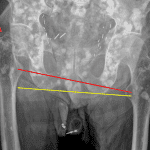

Age: 89

Sex: Male

Indication: Seizure, fall

- Acute, mildly varus impacted right subcapital femoral neck fracture with mild lateral displacement

- Mild degenerative changes of the hips and sacroiliac joints

- Numerous sclerotic lesions throughout the visualized osseous structures

- Osteopenia

- Multiple surgical clips overlie the anatomic pelvis bilaterally

- Penile prosthesis

- Subcapital femoral neck fracture

Acute, mildly varus impacted right subcapital femoral neck fracture with mild lateral displacement.

Mild degenerative changes of the hips and sacroiliac joints.

Numerous sclerotic lesions throughout the visualized osseous structures, consistent with osteoblastic metastatic disease.

Osteopenia.

Multiple surgical clips overlie the anatomic pelvis bilaterally.

Penile prosthesis.